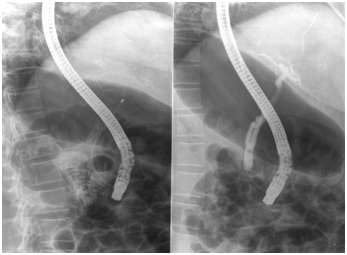

A 45 years-old woman was admitted to our hospital with right upper abdominal discomfort. She had undergone cholecystectomy a few years before and the laboratory findings evidenced: GOT 30 UI/l (n.v.<37),GPT 78UI/l(n.v.<40), gammaglutamyltranferase, GGT 330 UI/l (n.v. 537), alkalinephosphatase 220 UI/l (n.v. 53-128), total bilirubine 0.6 mg/dl (n.v. 0.2-1.2), RBC 4.64 106u/L (nv 4.40-5.60),Hb 11.9g/dl (n.v. 12.8-16.5), HCT 36.6 % (n.v. 40-50), WBC 7.64 193u/L, PT 107% ( n.v. 70-130), PT INR 0.95 (n.v. 0.90-1.30),PTT 30.0 sec(26.0 40.0), amylase 64, lipase normal value. Good general conditions with clinical history of hernia lumbar with NSAIDs irregular treatment and epilepsy in effective drug treatment. She was use of analgesics for headache. Indication for ERCP was placed for detection of biliary sludges in common bile duct (CBD) without dilatation of extrahepatic and intrahepatic bile ducts. Sphincterectomy was performed over a hydrophilic guide, without immediate complications with clearance of sludges from common bile duct by Dormia basket (Figure 1). Two hours later she developed severe right upper abdominal pain not being susceptible to common analgesics. She was not hyperpiretic with normal laboratory tests and no free air to Rx-ray abdomen carried out after about 4 hours of the procedure. There was no signs of peritoneal involvement to clinic examination. Since the abdominal persisted with a drop of 2.5 grams of haemoglobin, RBC 3.67 and HCT 29.5, WBC 12.08, amylase 57,GOT 57,GPT 130, GGT 213,alkaline phosphatase 178 and total bilirubin 0.5, a CT abdomen was performed. It highlighted a wide collection heterogeneously hypo-isodense with densitometric values of fluid type blood in the subcapsular right liver, between the posterior and anterior-medial area, without signs of active bleeding or capsular leak. No hemoperitoneum, no pneumoperitoneum, no dilated the intra and extrahepatic bile ducts (Figure 2). Large pleural effusion with hypoventilation lower lobe and posterior segment of right upper lobe (Figure 3). The patient still presented without fever with abdominal pain attenuation. On the surgeon input, conservative management was performed with intravenous fluid replacement and broad-spectrum antibiotics. After five days she presented fever and abdominal CT was unchanged from the previous control, except relief of subcapsular tiny gas bubbles. On this relation and the pulmonary compromission, she was under surgical treatment for hematoma and pleural effusion drainage. At surgery it was a massive subcapsular hematoma, partially coagulated, which covered the entire liver right and partially the fourth segment with intimate adherence to the diaphragm and lateral shower right. Pleural effusion was clear without bacterial infection. She was symptoms free with excellent postoperative course and was discharged after about 10 days after surgery with normality at laboratory parameters and abdominal ultrasound scan. Serial ultrasonographic and rx-ray examinations were performed with complete resolution of pleural effusion and pulmonary ventilation with persistently normal liver morphology at the end of 30th day. She remained asymptomatic at subsequent follow up.

Figure 1 ERCP cholangiography with Dormia basket in CBD and the tip of guide wire in the hepatic bile duct (arrow).

Two cases report pleural involvement, whose pathogenesis should be depended presumably from the inflammatory reaction resulting by the anatomical relationships between the pleural and the walls of the hematoma. In Almost all cases endoscopic procedures were performed by using a wire guide; howewer the type of wire guide is not specified. Bleeding disorders or special medical conditions or liver disease at risk for bleeding were not described. In nineteen cases the management of hematoma was conservative with a medical therapy with antibiotic and fluid infusion while in thirteen cases a percutaneous drainage was performed. Embolization is recorded in five cases. Surgical treatments were performed in eleven cases. There were recovery in forty-three patients; three patients deceaded. The pathogenesis of subcapsular hepatic hematoma is not clear. It is most likely due to the trauma of the tip of the guidewire resulting in puncture of liver parenchyma with rupture of small blood vessels, when it is pushed-on in the intrahepatic biliary tree in association with injection pressure of contrast medium. This might explain both the presence of air in the hematoma and the high frequency of bacterial contamination with the risk of abscess formation, as the procedure was performed under not sterile conditions. The endoscopic maneuvers with the guide wire should be conducted with caution and avoid to push the guide wire in the bile ducts higher than necessary, in not dilated biliary tree especially (Figure 1). By keeping in mind this complication, the careful management of the guide by endoscopist or his/her assistant is essential for avoiding its eccessive manipulation and the loss of the edge of the fluoroscopic distal image. The management of the complication depends to the size of hematoma, the patient's hemodynamic stability, the anemia degree, the presence of infection and the patient's general conditions. Its conservative management is usually effective if identified and treated rapidly with a multidisclinary approach of medical or interventional radiology and surgical input.17–59